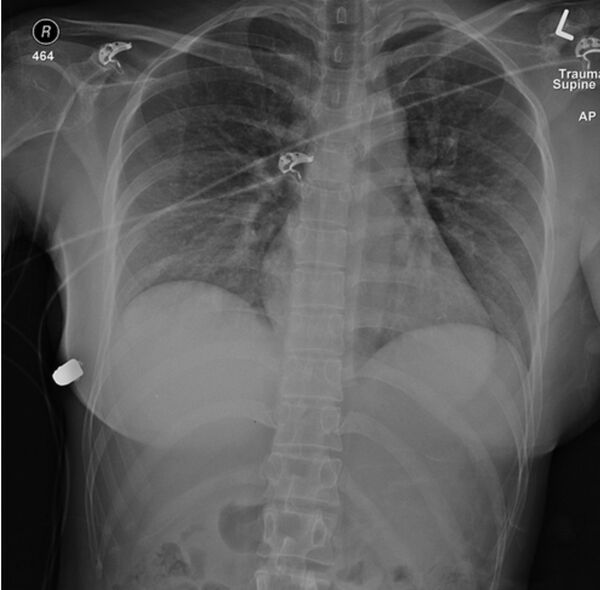

Các bác sĩ tìm thấy một vết đạn ngay bên trên vú trái và tìm thấy một viên đạn mắc kẹt trong cơ thể, dưới vú phải. Cô gái cảm thấy tình trạng cơ thể tốt một cách đáng ngạc nhiên, với vết thương như vậy.

Để loại bỏ viên đạn, các bác sĩ đã phải tháo cả hai miếng chèn silicon ra khỏi ngực bệnh nhân. Họ thấy kinh ngạc: các bác sĩ nhận ra viên đạn đã bị thay đổi đường đi để không bắn thẳng vào tim. Sau va chạm, viên đạn chuyển hướng đến đúng miếng silicon, xuyên vào ngực và bị mắc kẹt trong đó. Dấu vết của đạn được lưu giữ trong túi silicon cấy ghép.